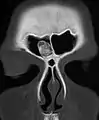

Osteoma of the frontal sinus on CT